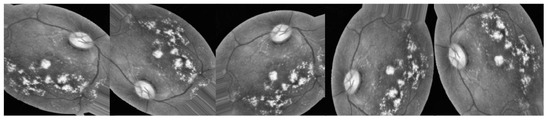

3.2.1. Preprocessing Using CLAHE and ESRGAN

- CLAHE

- ESRGAN

- Normalization